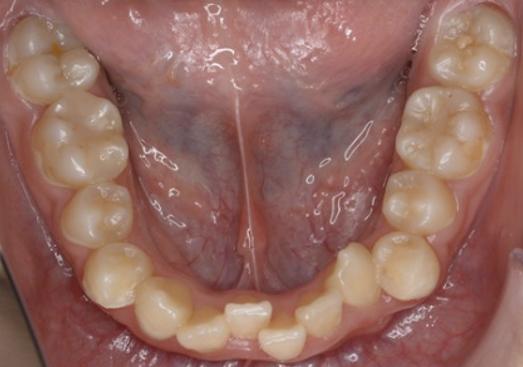

このような患者様の場合ですが、前歯部をIPRする必要があることはお分かりいただけると思います。

なぜなら、「叢生(歯の重なり)」がキツく、これでは歯を並べる事ができないから。